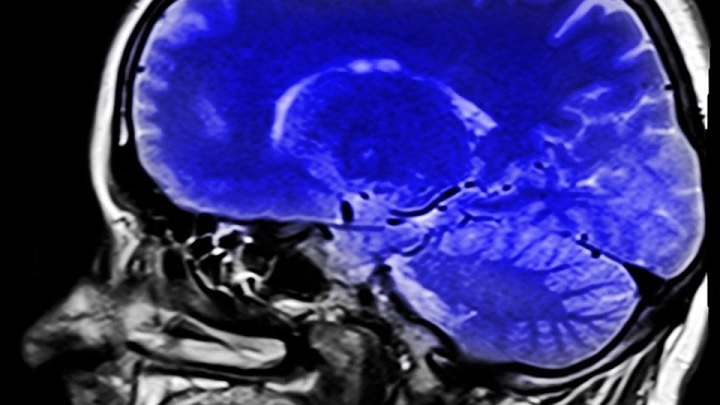

Муж-тиран изменился после удаления опухоли мозга

Пользовательница Reddit под ником @leekfluffy описала чудесные превращения, произошедшие с ее супругом после удаления опухоли мозга. Женщина написала, что ее муж с начала отношений был тираном, но совершенно изменился после операции.

Месяц назад мужчине удалили опухоль мозга и после операции он стал совершенно другим.